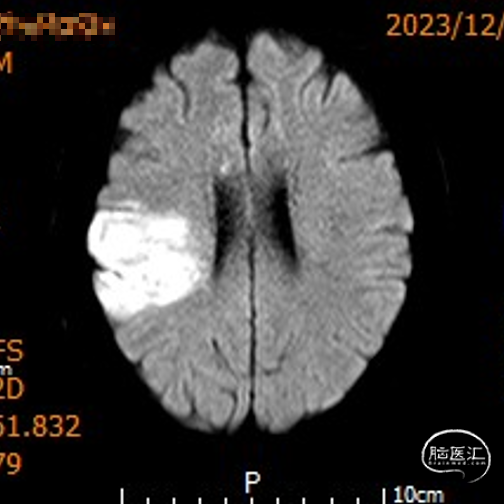

影像信息

颅脑CT示:

1.双侧侧脑室旁及右侧额顶叶多发脑梗死;

2.脑白质变性。

MRI示右侧颞顶叶及胼胝体急性脑梗死。